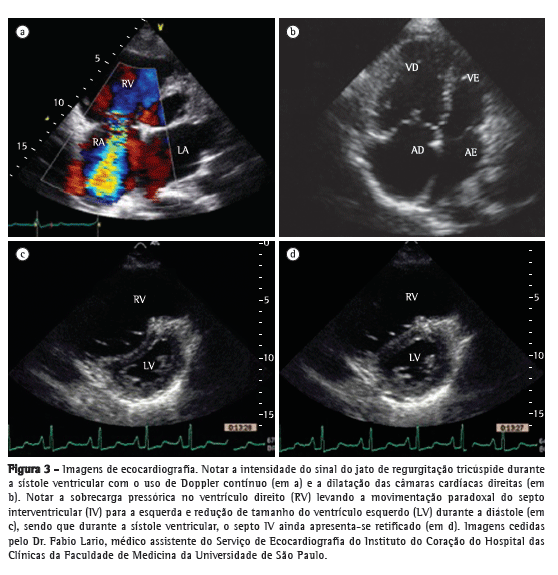

Contudo, a fração de ejeção e os volumes do VD não podem ser calculados usando as equações matemáticas normalmente aplicadas ao estudo do VE. Por esse motivo, diversos parâmetros ecocardiográficos foram desenvolvidos para avaliar a função do VD e a condição hemodinâmica da artéria pulmonar. O método mais praticado baseia-se na identificação da tricuspid regurgitation (TR, regurgitação tricúspide). A medida da TR fornece uma estimativa do gradiente pressórico entre as câmaras cardíacas direitas. Os primeiros trabalhos datam de meados da década de 80,(9,10) nos quais fora empregada a técnica de Doppler de onda contínua. A técnica consiste em medir a velocidade de pico da regurgitação tricúspide (VTR), que oferece uma estimativa do fluxo regurgitante do VD para o átrio direito (Figura 3). Aplicando-se a equação simplificada de Bernoulli (∆P = 4 × VTR2), é possível converter a medida de fluxo em uma estimativa de pressão. Adicionando a esse gradiente pressórico uma estimativa da pressão de átrio direito, obtém-se o valor da pressão sistólica de pico do VD (PsVD), uma aproximação da pressão sistólica de artéria pulmonar (PsAP), desde que ausentes obstruções na via de saída do VD. O resultado de PsVD > 35-40 mmHg é sugestivo de HP.(10) Na presença de fluxo regurgitante baixo, a estimativa da PsVD torna-se menos sensível, porquanto a intensidade de sinal de eco é baixa, o que pode subestimar os valores de pressão. Mas situações de TR muito intensa também podem subestimar as medidas de pressão porque resultam em equalização das pressões entre o átrio direito e o VD, dificultando o sinal ao Doppler. Por outro lado, o método também pode superestimar os valores de PsVD.

Outros sinais ecocardiográficos, como aumento das câmaras cardíacas direitas, derrame pericárdico, disfunção de VD, movimentação paradoxal do septo interventricular e redução dos volumes de enchimento do VE, também corroboram a presença de HP (Figura 3).(18) Guardadas suas limitações e bem avaliados e interpretados à luz do contexto clínico, todos esses parâmetros podem ter utilidade no diagnóstico e no seguimento de pacientes com HP.